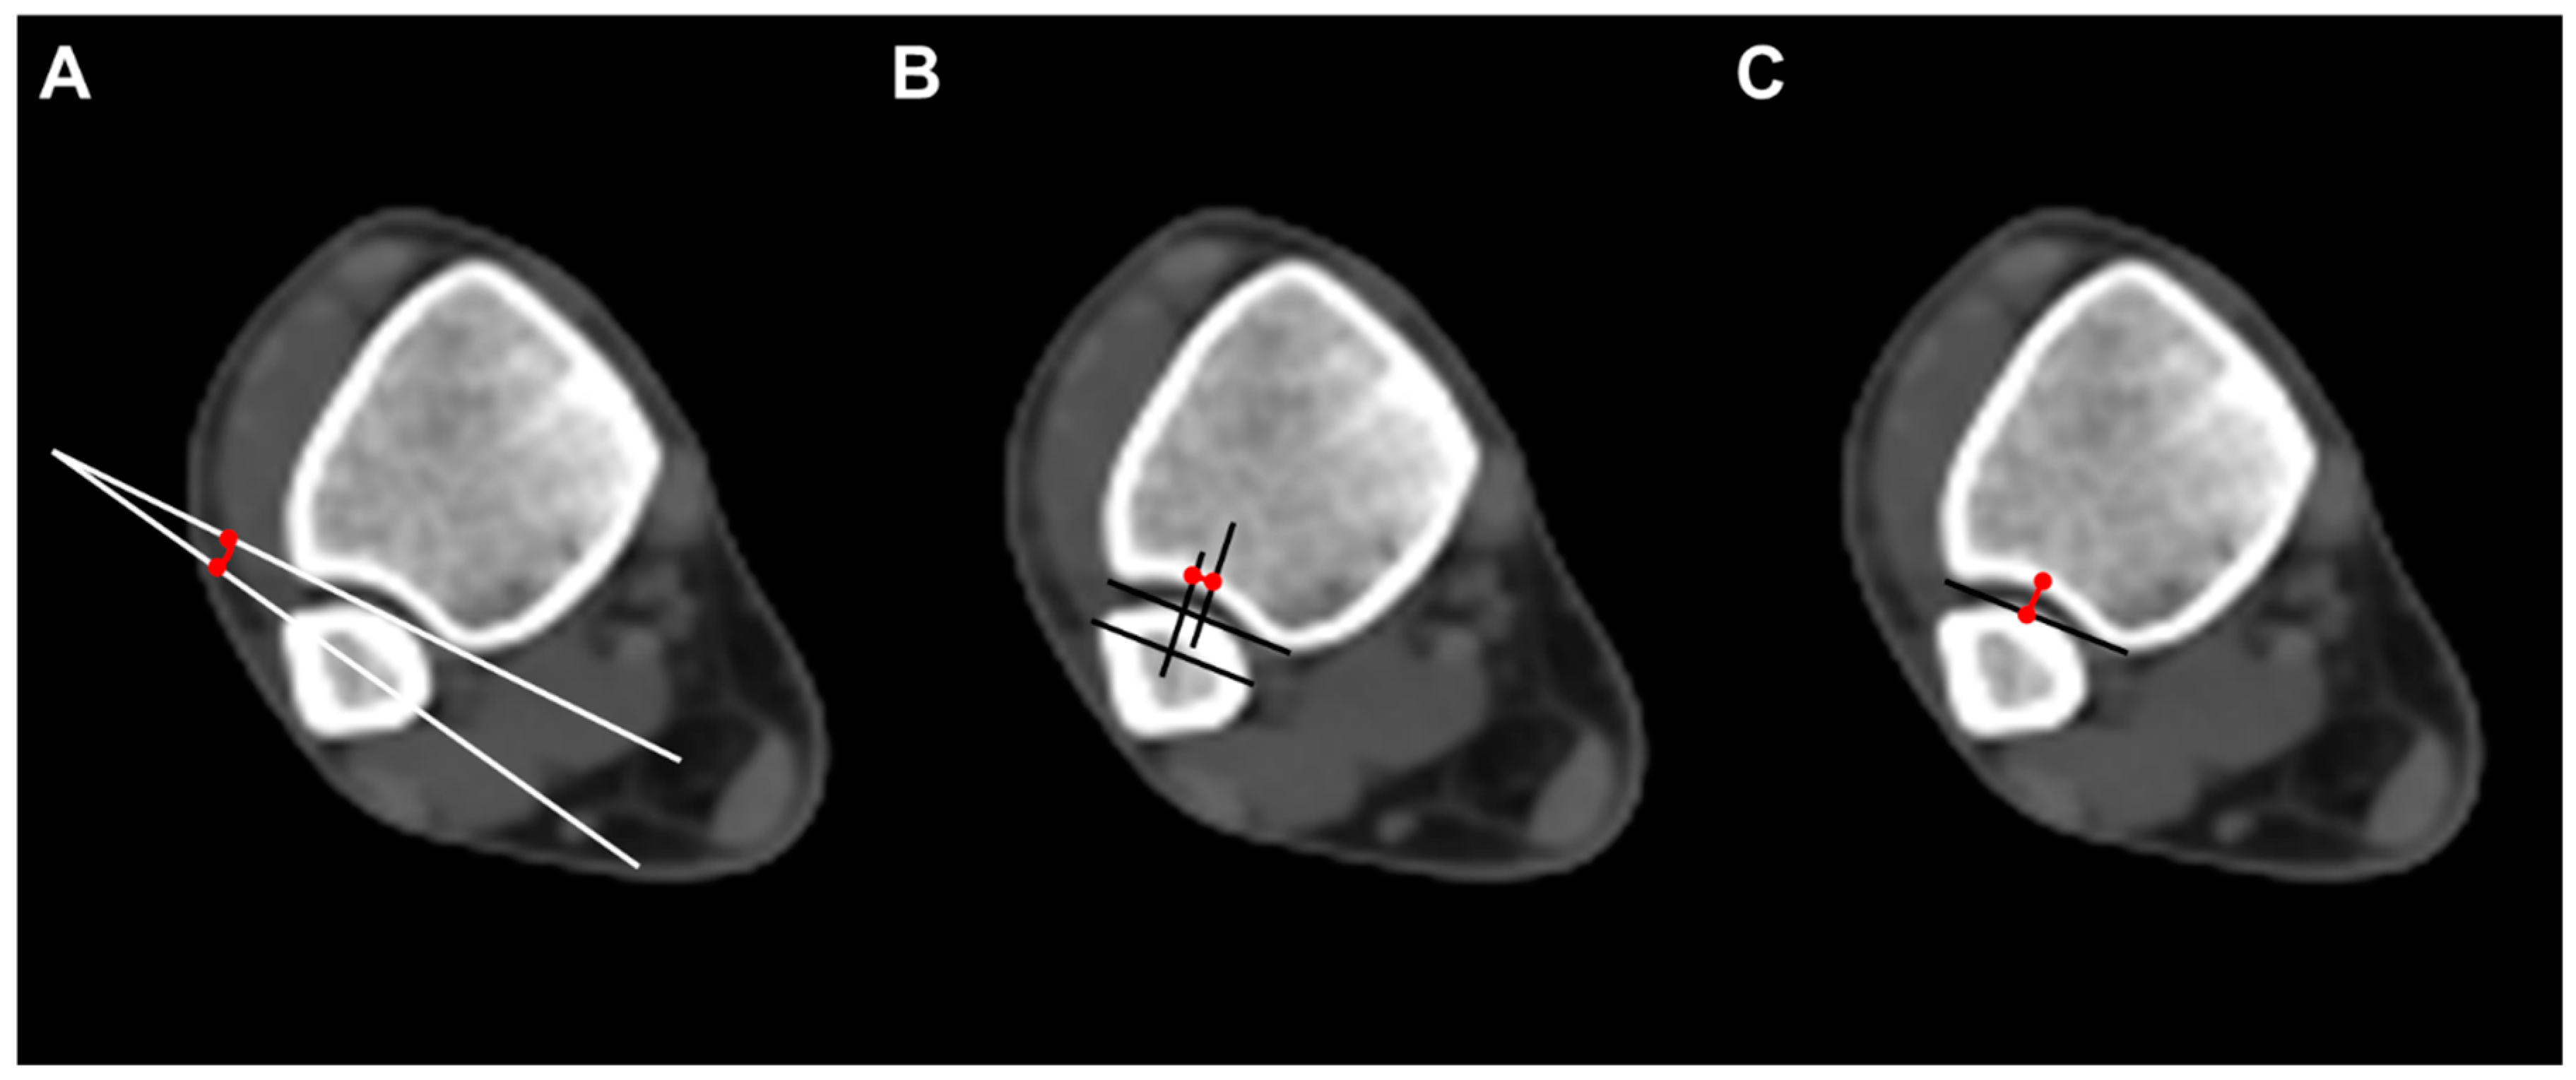

To evaluate the anatomical distal tibiofibular relationship, we measured three parameters on axial CT scan images. Fibular rotation (FR) was defined as the angle between a line drawn between the anterior and posterior borders of the incisura and the line through the anterior and posterior fibular tubercles. The angle was considered positive if the fibula was internally rotated compared with the incisura []. Sagittal translation (ST) of the fibula was measured as the difference between the midpoint of the incisura length and the midpoint of the fibular length line. The fibular length line was drawn from the most anterior point of the fibula, parallel to the incisura length []. Incisura depth (ID), which means the distance from the tibial cortex at the midpoint of the incisura to the line that joins the most anterior point with the most posterior point of the incisura, was also measured (Figure 2).

Figure 2.

Radiographic measurements. (A) Fibular rotation (angle between a line drawn between the anterior and posterior borders of the incisura and the fibular orientation line); (B) sagittal translation (difference between the midpoint of the incisura length and the midpoint of the fibular length line. The fibular length line was drawn from the most anterior point of the fibula, parallel to the incisura length); (C) incisura depth (distance from the tibial cortex at the midpoint of the incisura to the line that joins the most anterior point with the most posterior point of the incisura).